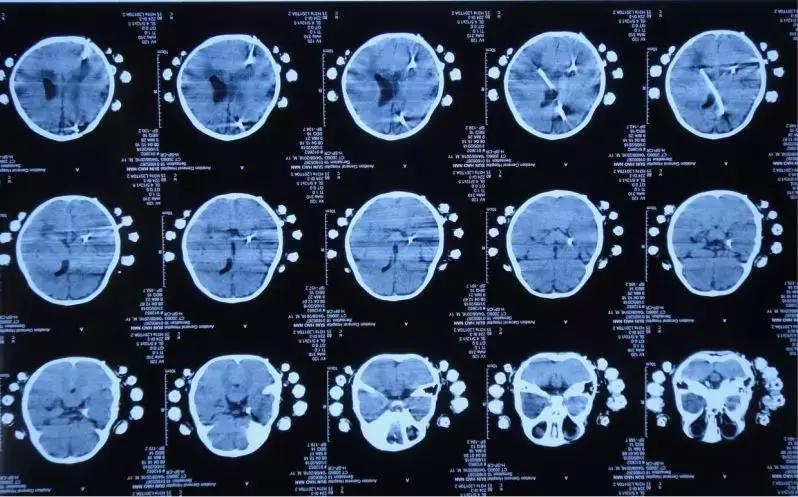

2018年5月2日头部影像检查

2018年5月2日患儿病情稳定 精神状态佳

李小勇主任指导意见:患者诊断“脑积水”明确。根据目前情况,患者脑脊液性质可,脑脊液细菌培养阴性,无发热及呕吐症状,2018年5月17日行脑室腹腔分流腹腔端置入术。

2018年5月17日头部影像检查

2018年5月31日头部影像检查

2018年8月19日来院复查,小浩浩康复如初,跟同龄小朋友无异样。

2018年8月19日复查头部影像